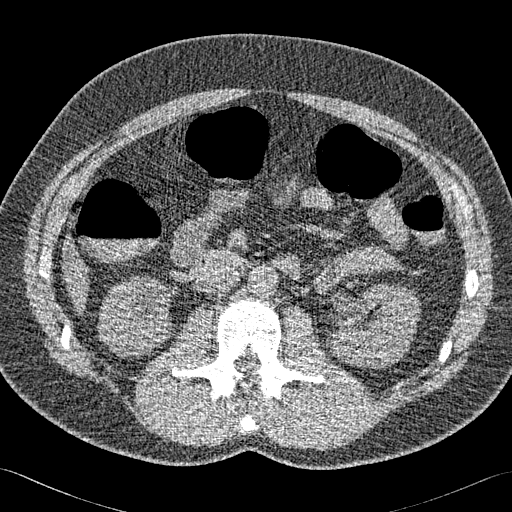

Elimination of noise in ultra low dose CT data

original section

after smoothing

The same data displayed using a different gray level window